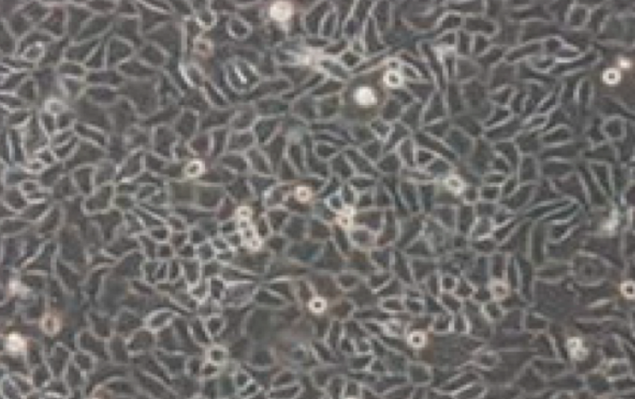

Capan-2;人胰腺癌细胞